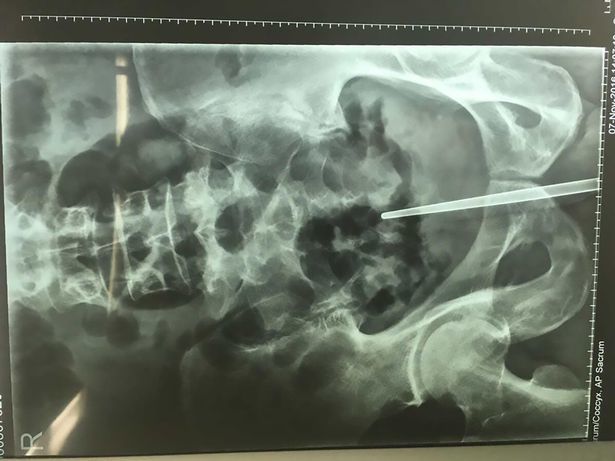

Hy hữu: Nhét đũa vào dương vật khi bạn nhậu thách đố

Trong lúc nhậu với nhóm bạn, người đàn ông dùng đũa dài 12 cm tự chọc vào dương vật của mình.

Cầu cứu bác sĩ vì đũa chui vào 'của quý'

Một người đàn ông phải vào bệnh viện nhờ bác sĩ cứu sau khi nhét một cây đũa vào trong sâu trong "của quý".